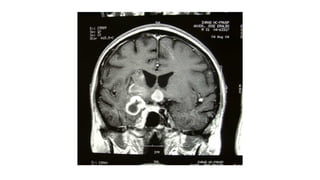

 SNC